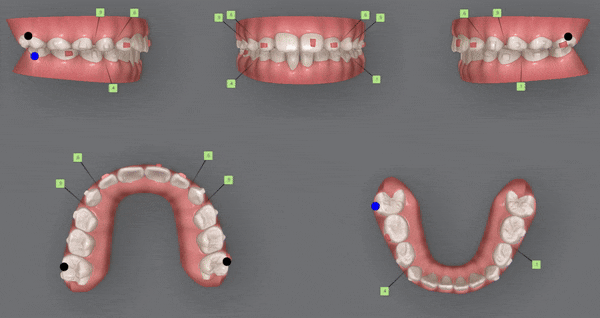

먼저 닥터킴의 정밀한 진단을 위해

i-TERO 로 구강내 스캔을 해보았습니다.

위 사진은 접촉되는 치아면을

spot 으로 표시해 확인해 볼수 있는데요,

노란원 안의 찍힌 spot들을 보니

아랫니가

윗니의 치아면이 아닌 입천장에 닿고 있었습니다.

아래 앞니의 잇몸 퇴축도 진행되고 있는 상황이었어요 ㅜ

1st Clincheck (27개)

23/8~24/1

인비절라인은 ' 클린체크' 프로그램을 통해

어린이의 교합 및 정렬의 치아 관계를 평가하고, 어떻게 발전할지 예측할 수 있습니다.

첫번째 클린체크에서는 27개의 장치로 마무리 해드렸습니다.

치아가 너무 깊게 물리는 과개교합이

눈에 띄게 개선된 모습을 확인해 보실 수 있습니다 :)